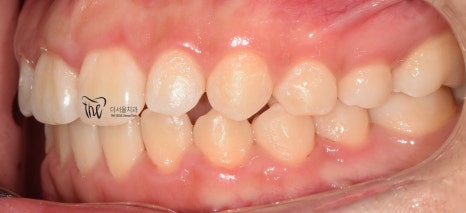

그리고, 정면 및 측면에서 본 모습으로는

살짝 개방교합(Open bite)의 형태를 보여줍니다.

그러면서, 치아들 간의 공간이 조금씩

떨어져 있는 것을 볼 수 있습니다.

마치, 치간이개와 같은 느낌을 받을 수 있으며

앞니들이 앞쪽으로 많이 뻐드러져 있는 형태를

띄고 있습니다.

이럴 경우에는, 무턱 의 증세가 더 뚜렷하게

나타날 수 밖에 없는 상황이 됩니다.

앞니들의 뻐드러짐이 많이 개선이 됨에 따라서,

이제 조금은 가지런한 치열이 만들어지는 것을

보고 계십니다.

다만, 어금니의 위치 이동이 아직 다 되지

않았기 때문에 측면에서 확인했을 때는

치아들 사이에서의 공간이 떠 있으면서,

약간은 1치대 1치 교합 관계가 만들어져

있는 것을 볼 수 있습니다.